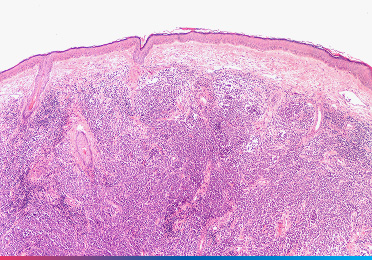

Da das MCC klinisch schwer von anderen Hauttumoren zu unterscheiden ist, bringt erst die feingewebliche Untersuchung (Biopsie) Gewissheit.

- Histologie und Immunhistochemie: Unter dem Mikroskop zeigt das MCC typische Merkmale (“kleinzelliges Karzinom”). Zur sicheren Abgrenzung – etwa von Lungenkrebs-Metastasen – werden spezielle Färbungen eingesetzt (typischerweise Cytokeratin 20 [CK20]-positiv und Thyroid-Transkriptionsfaktor-1 [TTF-1]-negativ).